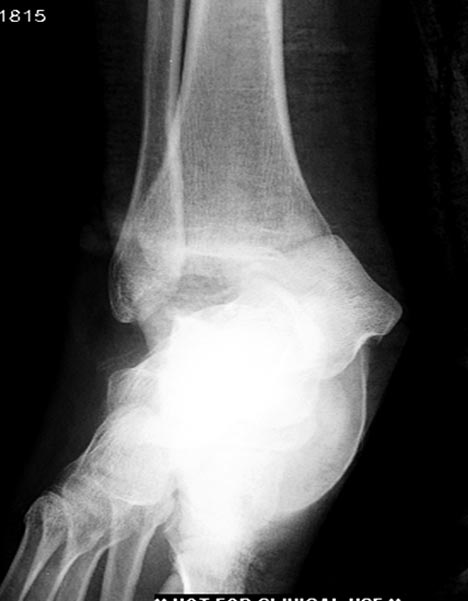

6 день госпитализации-операция на таранной кости.

На 9й день фиксация дистального бедра, где фрагмент Hoffa и вертикальный перелом надколенника, зафиксированы винтами.